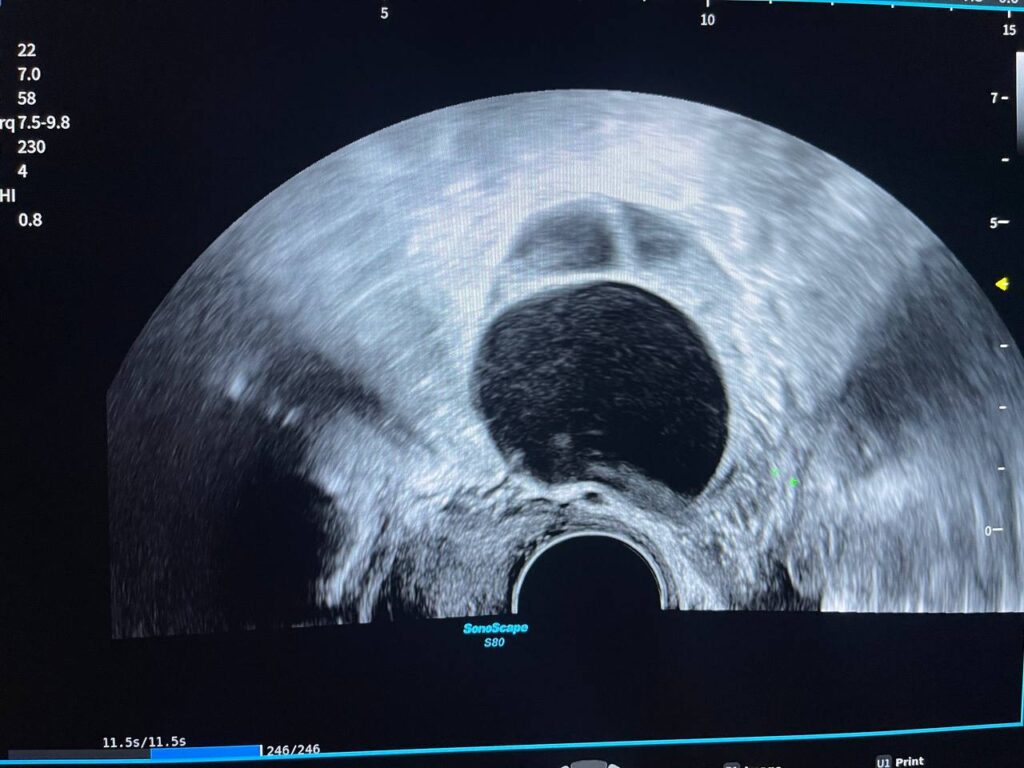

Presence of hyper vascular mass 47x31mm in the right cornua & within the interstitial layer , picture mostly of ectopic H Mole pregnancy , please for further study

Presence of hyper vascular mass 47x31mm in the right cornua & within the interstitial layer , picture mostly of ectopic H Mole pregnancy , please for further study